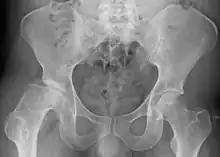

| Radiograph of a person with Legg–Calvé–Perthes disease | |